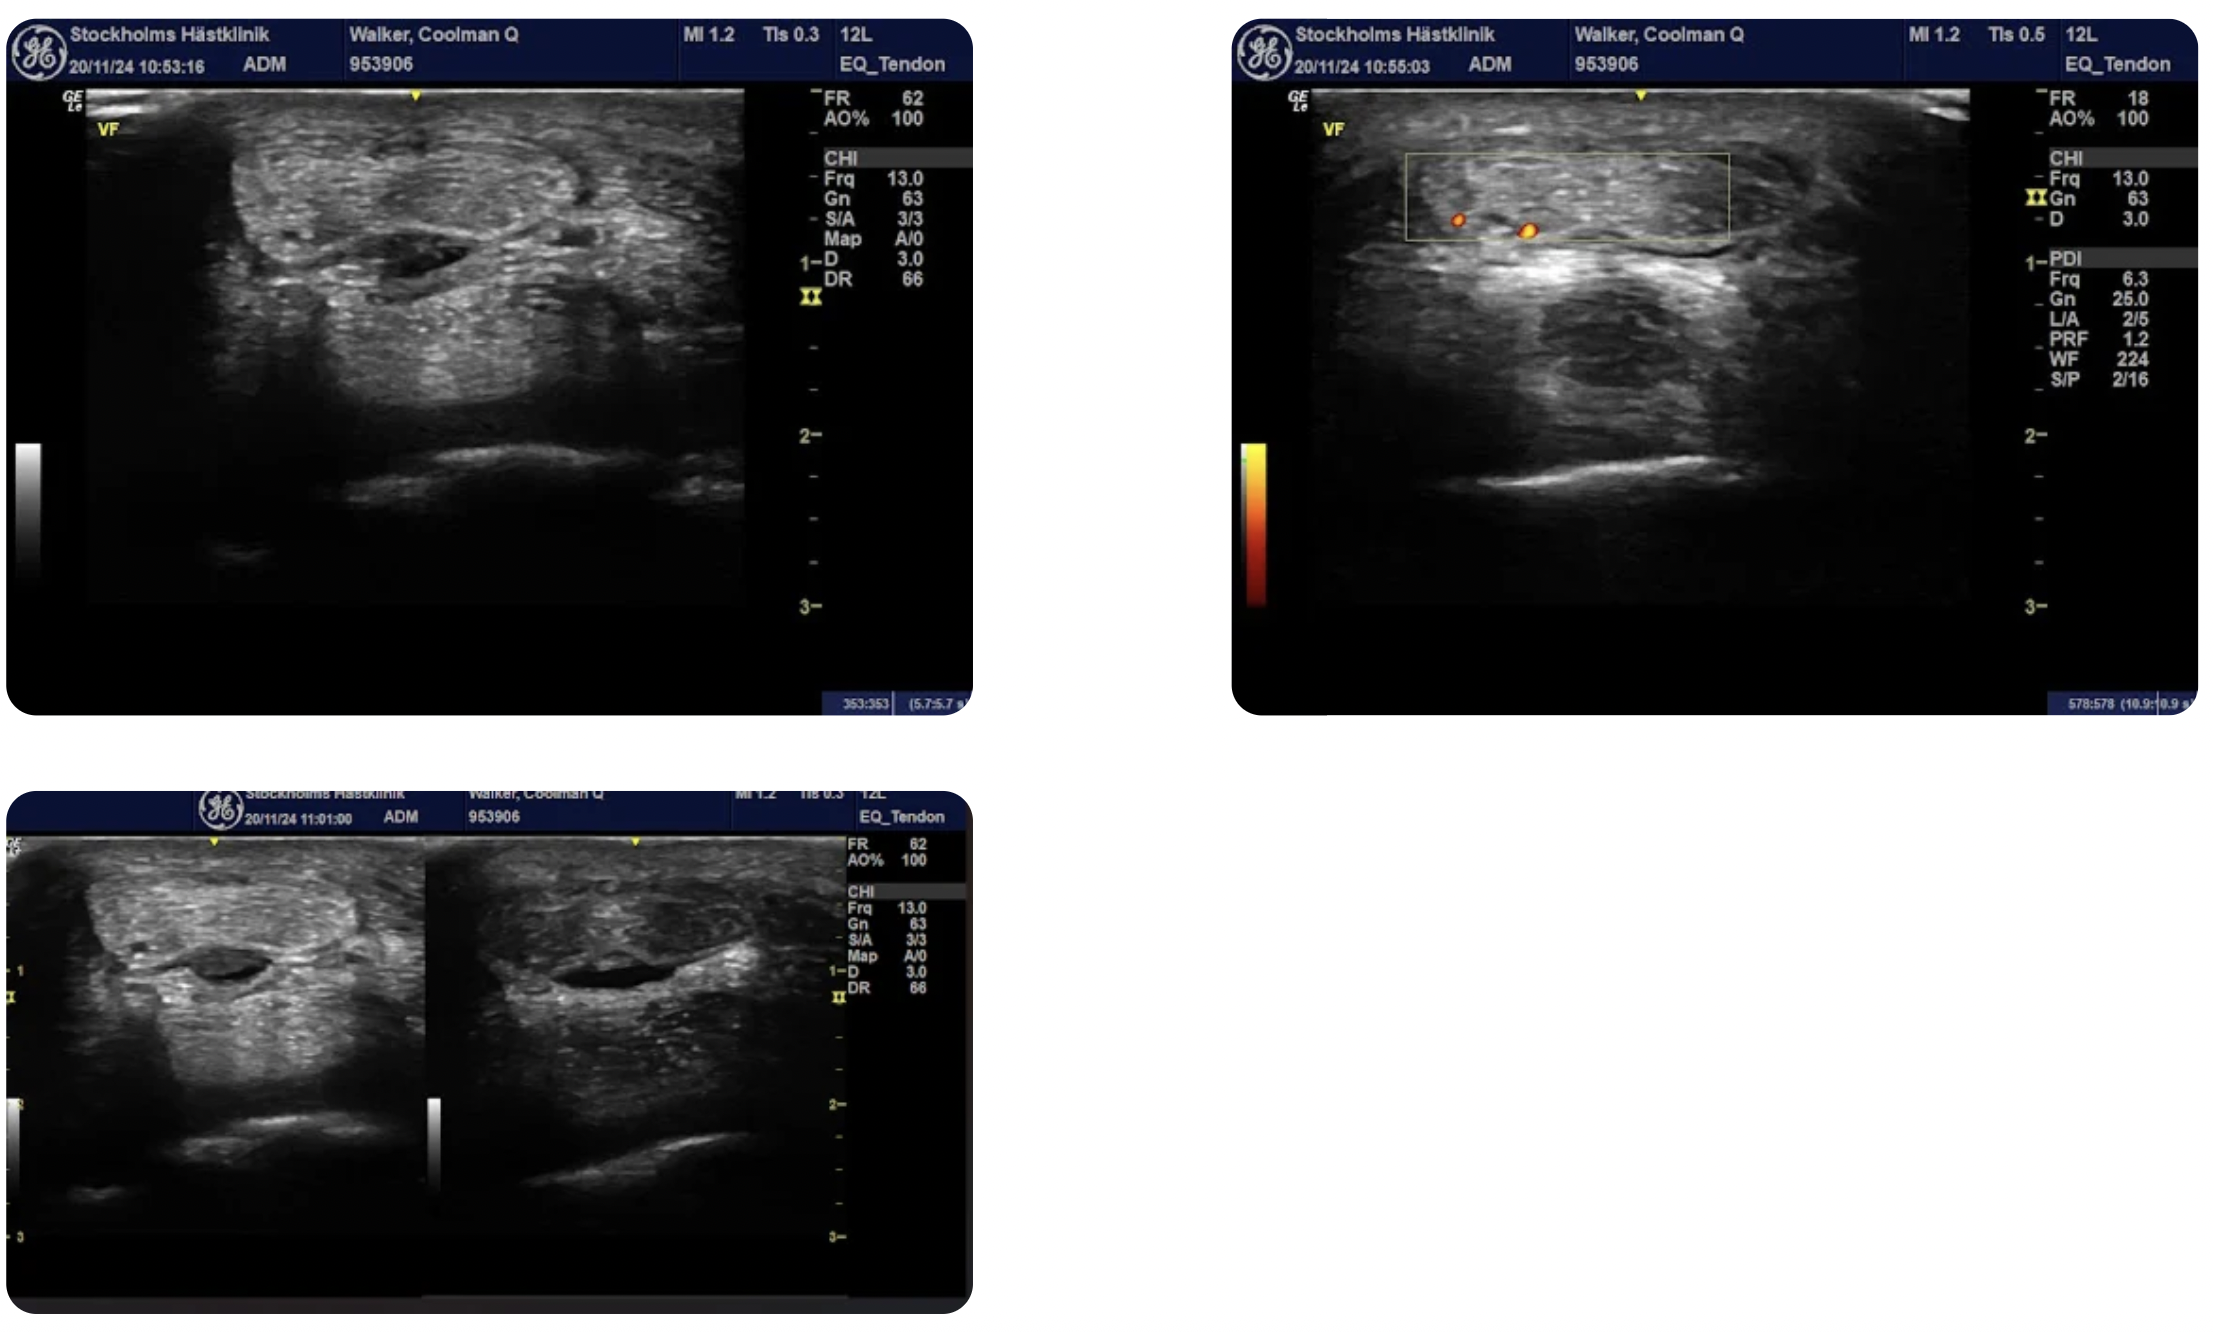

Coolman Q has since undergone treatment with corrective shoeing, navicular bursa injections, shockwave therapy, and a controlled exercise program. He is progressing well in his rehabilitation.

Regular follow-ups and monitoring with Sleip help ensure that he is progressing well in his rehabilitation.